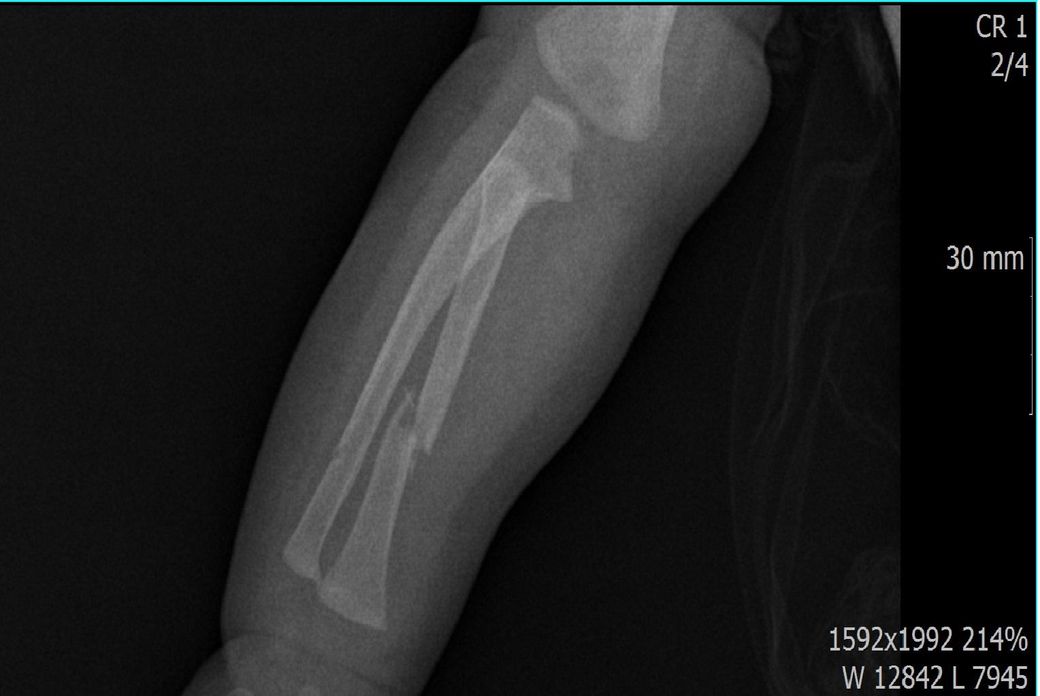

다름이 아니라, 첨부드린 엑스레이(X-ray) 사진처럼 골절 사실을 알게 되고 골절 발생 시점 대략적으로나마 추정시기를 파악하려고 문의 드리게 되었습니다

1) 3월 30일 촬영한 X-ray만으로 정확한 골절 시기를 100% 특정하는 데에는 한계가 있다는 점 충분히 인지하고 있기에 촬영날짜 기준으로 대략적으로 어느정도 시점에서 발생되었을 것으로 추측(ex 당일, 7~10일전, 7~14일 전, 10일 ~ 20일전, 14일 ~ 30일전 등등등)되는지 이해하고 싶습니다.

• 1번 째 사진

하지만 엑스레이 사진을 보고 골절시기를 추적하는 것은 무리입니다. 의사가 협조가 되지 않는 것이 아니라 단순하게 무리입니다. serial 사진이 있다면 가골형성 패턴을 보면서 추정이 가능할 것이겠지만 이 경우는 해당이 되지 않습니다.

단지 2번째 사진을 보면 척골이 완전히 부러져서 어긋나 있는 것이 보이지요? 통증이 심했을 것이며 (환자분이 어린 것 같은데 증상 호소가 더 심했겠지요) 팔이 많이 부었을 것입니다. 증상을 기준으로 생각하시면 더 정확하실 것 같습니다.